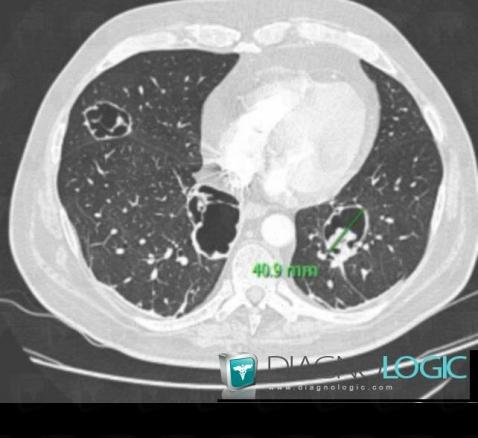

Pneumocystosis, Pulmonary parenchyma, CT

Here is the specific information in the key image above:

- Diagnosis Pneumocystosis, Location(s) Pulmonary parenchyma, with gamuts Cavitary pulmonary nodule, Multiple pulmonary nodule, Intracavitary pulmonary nodule / mass